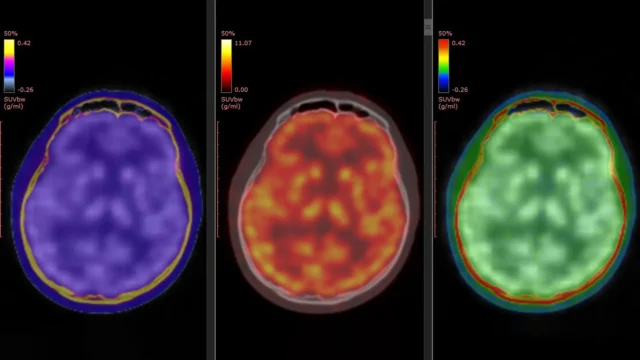

Um novo estudo publicado em Psiquiatria molecular Em 5 de março de 2026, ele tentou explicar esse mistério. O estudo foi liderado pelo professor Takuya Takahashi, do Departamento de Fisiologia da Escola Médica da Cidade de Yokohama, no Japão. A equipe usou uma técnica avançada de imagem de tomografia por emissão de pósitrons (PET) para observar diretamente as alterações no receptor de glutamato do ácido propiônico α-amino-3-hidroxi-5-marcado-4-isoxazol (AMPAR). Este receptor é uma proteína chave que ajuda a regular a comunicação entre as células cerebrais e desempenha um papel importante na plasticidade sináptica e na sinalização glutamatérgica em pacientes que recebem cetamina.

O estudo contou com um traçador PET desenvolvido anteriormente pela equipe conhecido como (¹¹C)K-2. Este rastreador permite aos cientistas visualizar AMPARs na superfície das células diretamente no cérebro humano vivo. Estudos anteriores em laboratório e em animais demonstraram que os efeitos antidepressivos da cetamina estão relacionados à atividade AMPAR. Um novo estudo fornece a primeira evidência direta de que esse processo ocorre em humanos.

Os pacientes receberam cetamina intravenosa ou placebo por duas semanas. Imagens PET do cérebro foram realizadas antes do tratamento e novamente após a última infusão. Esta abordagem permitiu aos pesquisadores comparar as mudanças no nível e distribuição de AMPARs no cérebro ao longo do tempo.

A cetamina não produziu mudanças uniformes em todo o cérebro. Em vez disso, as melhorias nos sintomas depressivos foram associadas a ajustes dinâmicos específicos da região nos níveis de AMPAR. Algumas áreas do córtex cerebral apresentaram aumento da densidade de receptores, enquanto áreas associadas ao processamento de recompensas, especialmente a habênula, apresentaram diminuição. Estas mudanças regionais estiveram intimamente associadas à melhoria dos sintomas depressivos dos pacientes.

“O efeito antidepressivo da cetamina em pacientes com DRT é mediado por mudanças dinâmicas nos AMPARs no cérebro humano vivo”, explicou o professor Takahashi. “Usando um novo rastreador PET, (11C)K-2, conseguimos visualizar como a cetamina altera a distribuição de AMPARs em regiões específicas do cérebro e como essas alterações se correlacionam com a melhora dos sintomas depressivos.”